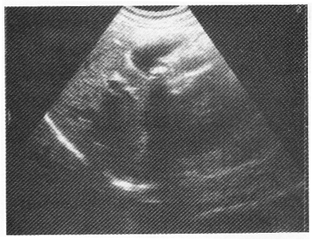

女性,30歲,反復右上腹疼痛2年余,反射至肩背部疼痛;超聲檢查如圖所示。

6.根據超聲圖像診斷為

A.膽囊息肉

B.膽囊癌

C.膽囊結石

D.膽囊蛔蟲

E.膽囊腺瘤

正確答案:6.C;7.C;8.E解題思路:1.該例臨床癥狀無特異性,超聲圖像是典型的結石表現。

2.膽囊結石與膽囊息肉超聲鑒別最主要點是:結石隨體位改變而移動,膽囊息肉生長在膽囊壁上不隨體位改變而移動。

3.膽囊腫瘤可因表面有鈣鹽沉積而表現為強回聲,但多不伴聲影,重要的是不隨體位改變而移動;結石隨體位改變而移動。